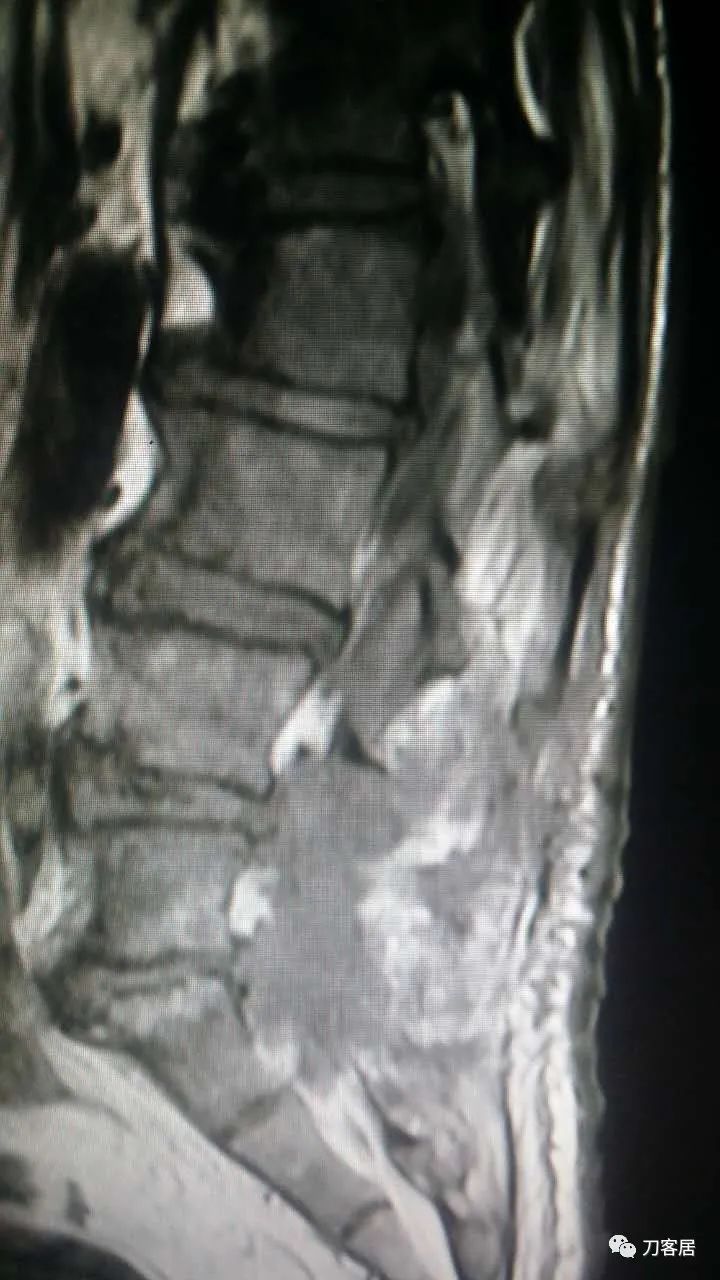

加注图21. MRI显示胸9-10和腰1-2椎管内后方占位病变,考虑血肿形成。

加注图22. MRI显示胸9-10和腰1-2椎管内后方占位病变,考虑血肿形成。

这个患者是我们西京医院骨科一位老教授在福建老家的哥哥,2015年8月份,他因为腰椎间盘突出症到福建泉州东南医院找黄约嘉主任做手术。手术很顺利,术后发生腰1-2和胸9-10椎管内血肿,手术平面以上两处椎管内血肿,当时他咨询我,我建议直接打开,切口向上延伸,清理血肿。我们科的老教授给他建议,两处血肿,用两个切口打开,进行血肿清理。最后他问我,是否可以穿刺抽吸血肿,我如实给他说,我自己没做过,但理论上是可以的,因为只要血肿没有凝固,是可以抽吸出来的。他当时晚上一直在纠结,本来想请麻醉医生帮忙穿刺,麻醉科医生没把握,后来是黄约嘉主任自己在CT引导下两处穿刺把血肿抽吸出来后患者症状缓解,血肿治愈。

术后第二天拔出引流管,术后第四天出现右下肢酸胀,夜间即使使用安定,也不能入睡,然后向我咨询,并做进一步检查,发现是椎管内血肿,血肿范围有两处,一处是胸9-10,另一处是腰1-2椎管内,最后,在两个部位进行穿刺,胸9-10平面穿刺,抽吸出4ml积血,腰1-2平面穿刺抽吸出6ml积血,血肿抽吸引流后治愈。